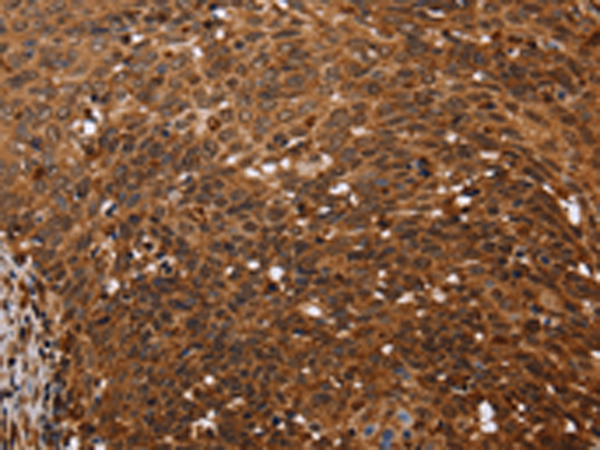

分类: 科研抗体货号: P08292别名: endocan应用: IHC反应种属: Human

分类: 科研抗体货号: P08306别名: LFG; LFG2; NGP35; NMP35; TMBIM2应用: WB,IHC反应种属: Human, Mouse, Rat

分类: 科研抗体货号: P08311别名: FAF应用: IHC反应种属: Human